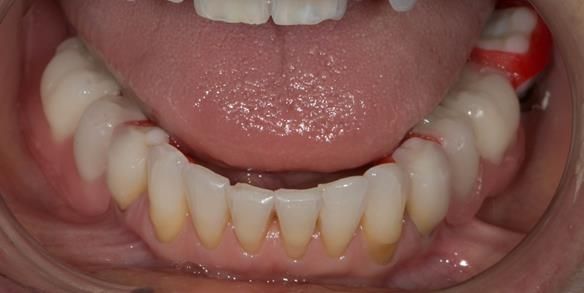

This newsletter describes in step by step detail Angela's transition through immediate partial dentures to crown supported definitive metal based dentures.

The clinical situation and treatment process is shown in detail below with photographs. I (Finlay Sutton) provided the clinical work and Rowan Garstang provided the technical work.